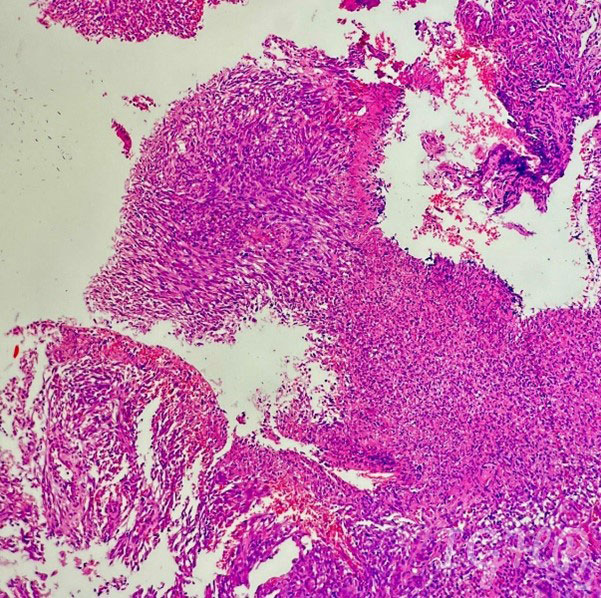

Microscopic Images-

Histology images showed bits of ulcerated small bowel mucosa with presence of proliferated spindle cells in ulcer bed.